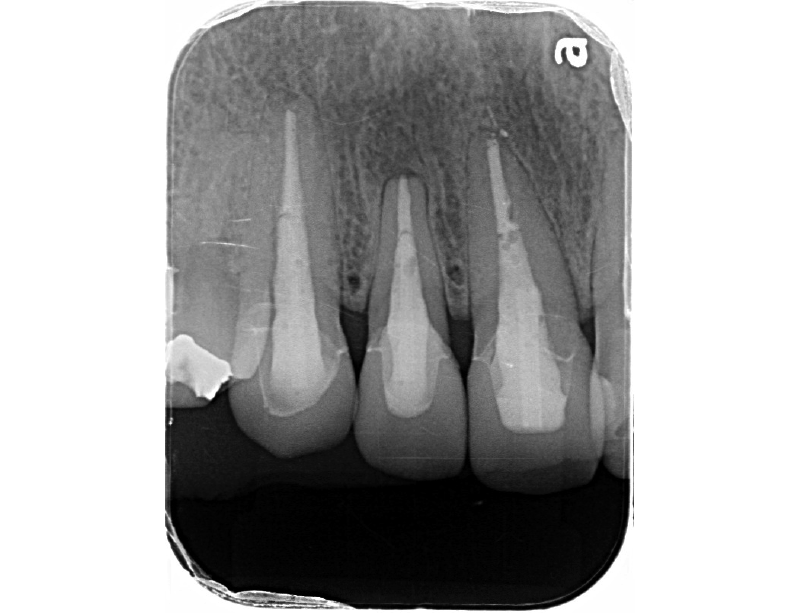

術前のレントゲン写真です。

術前のレントゲン写真です。虫歯が歯の神経(歯髄)に近接しているのがわかります。